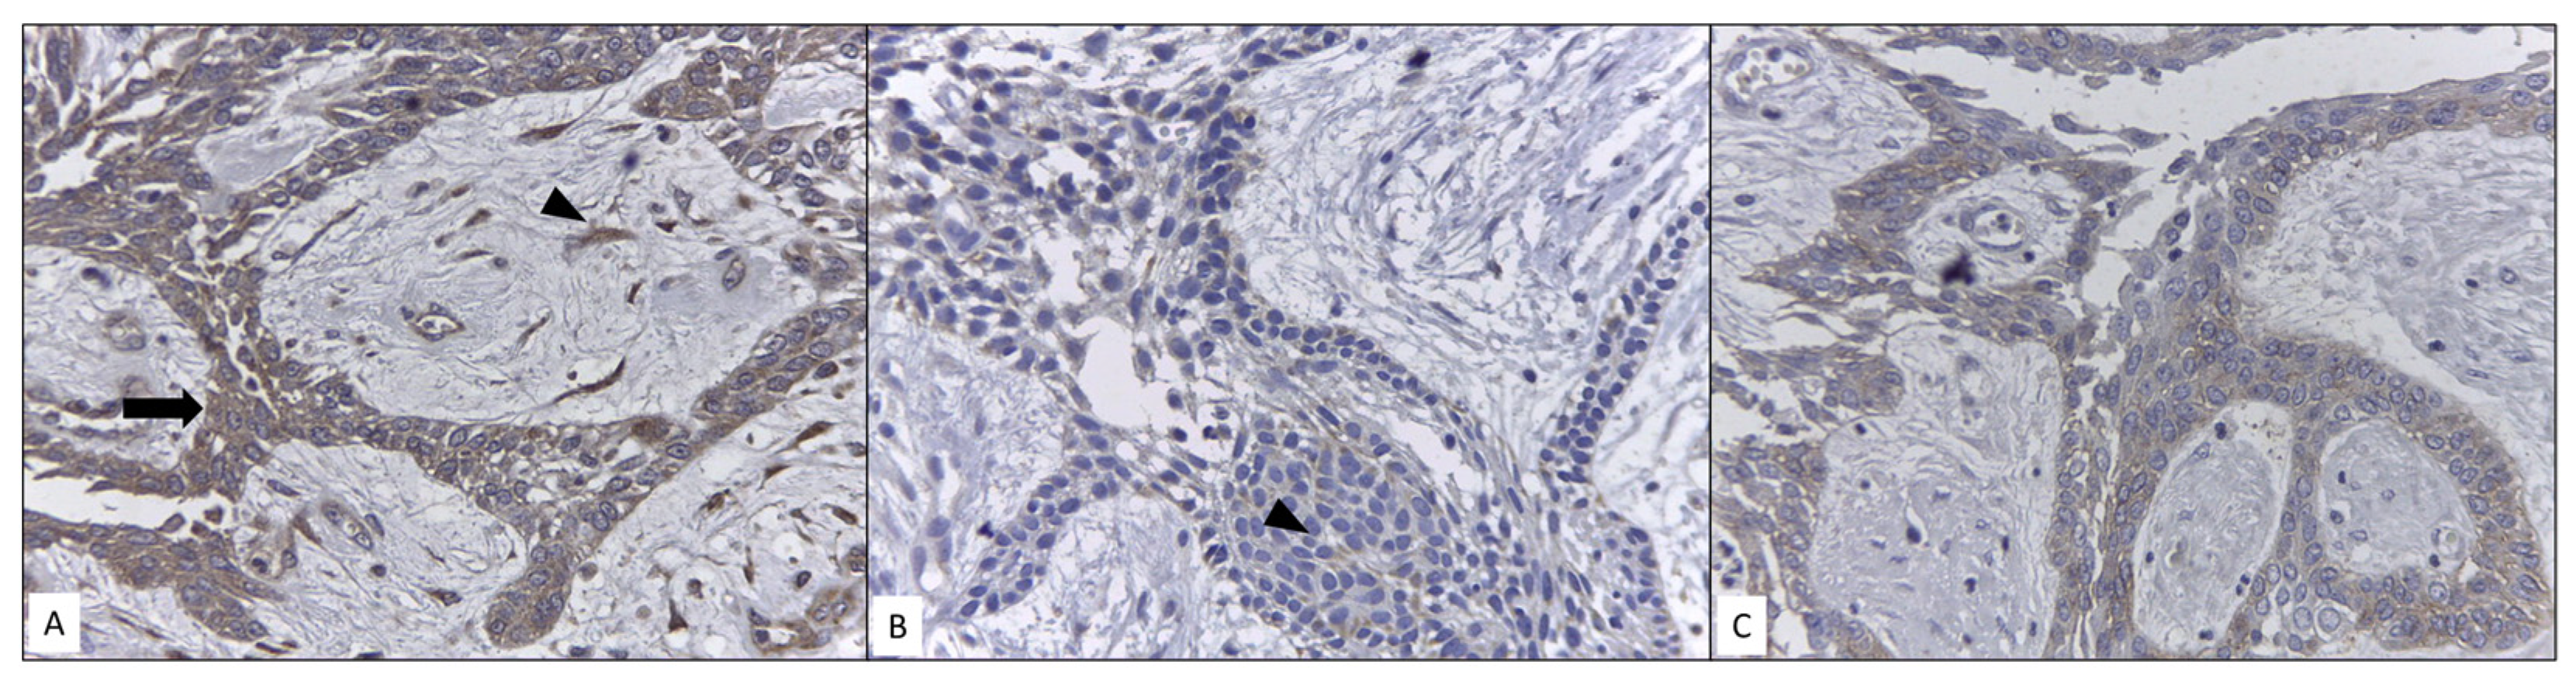

3.5. Immunoexpression Analysis